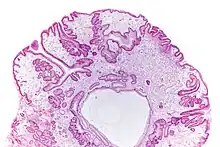

Micrograph of a gastric juvenile polyp, as may be seen in juvenile polyposis syndrome. H&E stain

Juvenile polyposis syndrome is an autosomal dominant genetic condition characterized by the appearance of multiple juvenile polyps in the gastrointestinal tract. Polyps are abnormal growths arising from a mucous membrane. These usually begin appearing before age 20, but the term juvenile refers to the type of polyp (i.e. benign hamartoma, as opposed to adenoma for example), not to the age of the affected person.[1] While the majority of the polyps found in juvenile polyposis syndrome are non-neoplastic, hamartomatous, self-limiting and benign, there is an increased risk of adenocarcinoma.